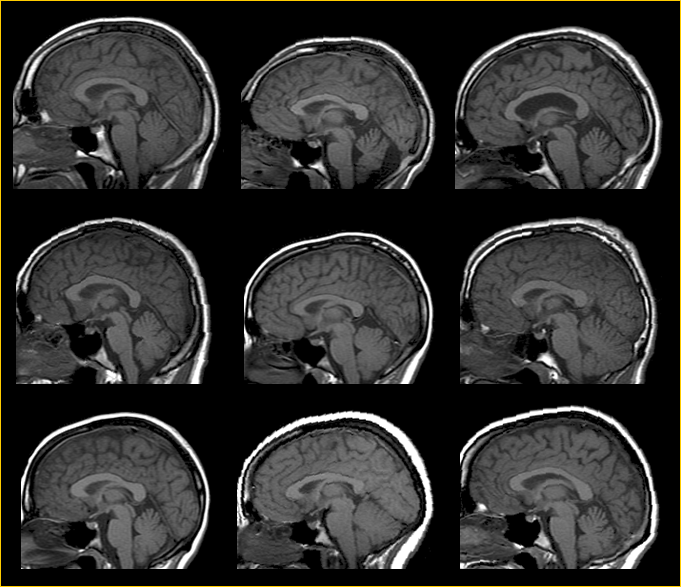

2、不同的人,脑袋大小形状都不一样,不同次的扫描,脑袋的摆放位置也不一样,如图1所示,图源对应位置值相减,再通过假设检验来得到的。

也就是说,如果所有被试的图像相同空间坐标对应的解剖位置不基本一致,即没有一致性,那相减得到的差异是没有意义的,无法进行进一步统计分析。所以需要让所有被试的脑袋在不失皮质特征差异的前提下,都对齐到标准模板上,以校正大脑整体形状和解剖位置的差异。让不同的被试,不同的扫描之间具有可比性或者一致性。

图1.大脑形状位置差异